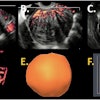

Making use of radiomics, an artificial intelligence (AI) algorithm can accurately differentiate between benign and malignant thyroid nodules on ultrasound examinations, perhaps even better than some radiologists can. This is the key finding of AI research published recently by the European Journal of Radiology.